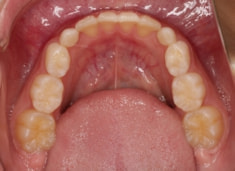

骨年齢は実年齢よりも低めなので、今後下顎の旺盛な成長が見込まれます。

検査時のレントゲン分析では、上下顎の関係は、上顎の劣成長があり下顎前突傾向という値がでておりましたが、前歯ジャンプ後はフェイスマスクの効果もあり、上下顎の関係は正常化しています。

上顎が若干優位になっていますので、今後の下顎の成長のための貯金になっているくらいです。